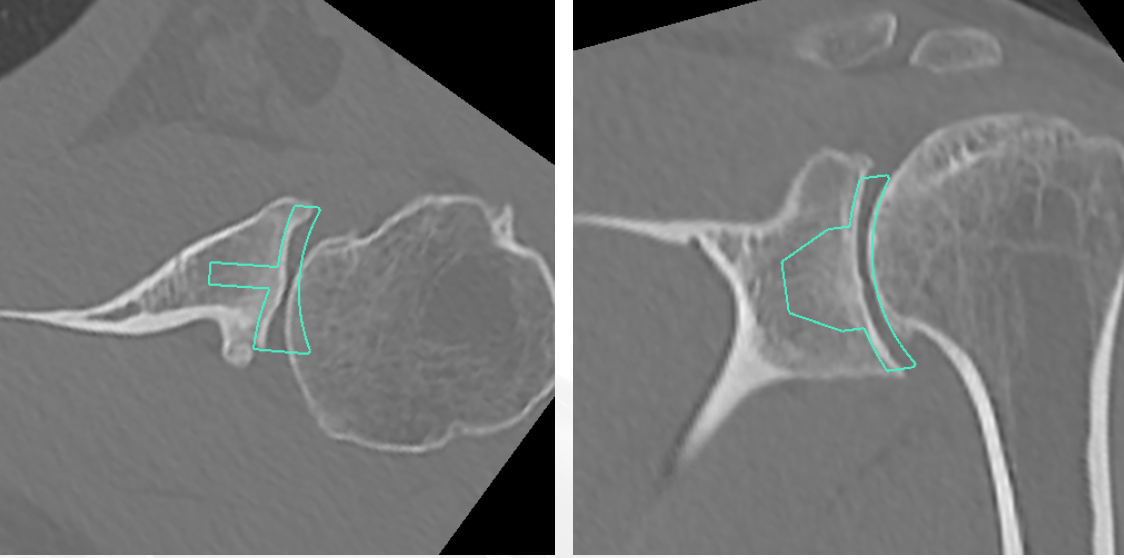

Glenoid version measurement

1. Xray v CT

- glenoid version axillary xray v CT

- glenoid retroversion overestimated on xray in 86%

- mean difference in measurements between xray and CT was 6.5o

2. Include scapula

Chalmers et al. J Should Elbow Surg 2017

- 14 B2 glenoids

- glenoid version measurement accurate if > 50% of the scapula width included

3. Measurement techniques

a. Friedman method

- tip of the medial border of the scapula to the midpoint of the glenoid fossa

b. Scapula body method

- intersection of the scapula body axis and the glenoid surface

- 3o difference in measurement of glenoid version between the two

- excellent reliability for both measurement techniques

c. Glenoid vault method

- tip of scapula vault to centre of glenoid

Automated 3D measurement of version

- automated software 3D measurement versus 2D Friedman method in 60 shoulders

- mean difference of 2o

- 3D software reliable and accurate